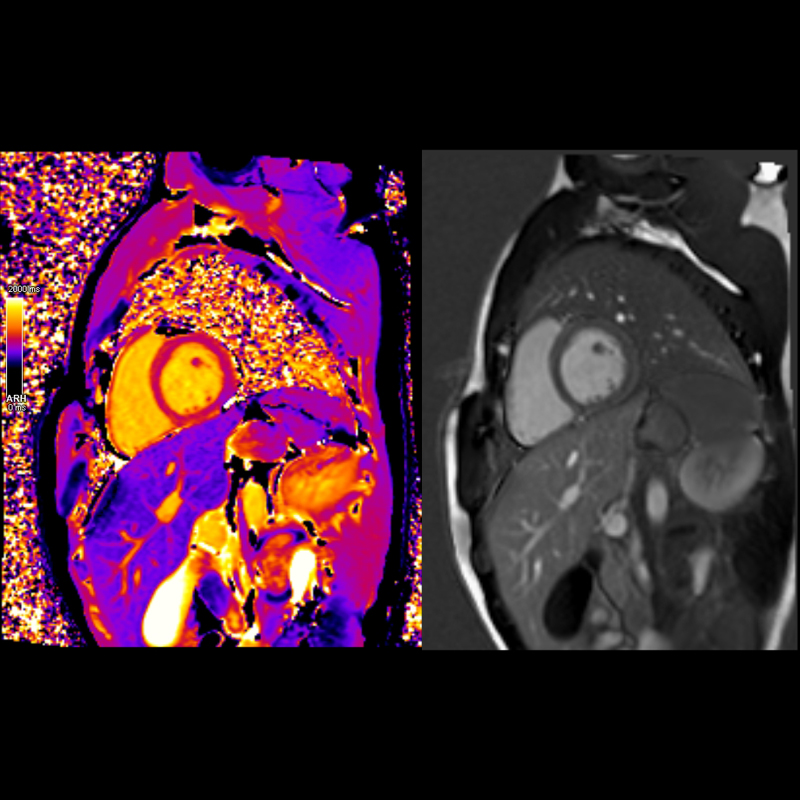

Kardiyolojik değerlendirmelerde detaylı kalp yapıları ve akım ölçümleri sağlar.

o Kardiyolojik değerlendirmelerde detaylı kalp yapıları ve akım ölçümleri sağlar.

Fonksiyonel ve Spektral Analiz:

Beyin fonksiyonlarını (fMRI), doku metabolizmasını (MR spektroskopi) ve kan akışını değerlendirmek için uygundur.

3. Fonksiyonel ve Spektral Analiz:

o Beyin fonksiyonlarını (fMRI), doku metabolizmasını (MR spektroskopi) ve kan akışını değerlendirmek için uygundur.